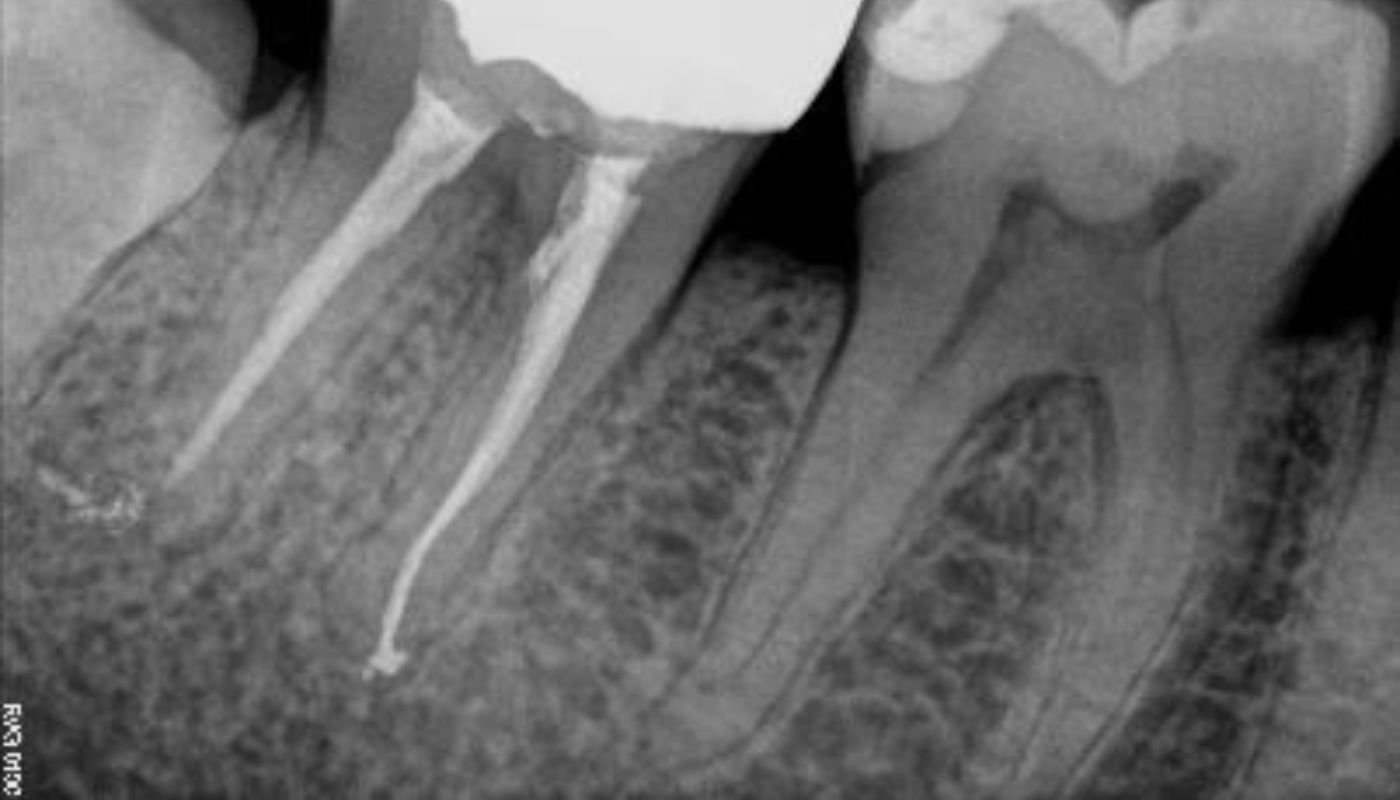

Talvolta la terapia endodontica deve essere applicata su denti già devitalizzati al fine di risolvere infezioni (dette lesioni apicali) che insorgono per pregresse cure canalari non congrue. In questo caso si parla di ritrattamento canalare, esso implica la rimozione del materiale precedentemente introdotto, una nuova alesatura, pulizia, sagomatura, chiusura dei canali e verifica radiografica dell’avvenuta guarigione a distanza di 6/8 mesi.